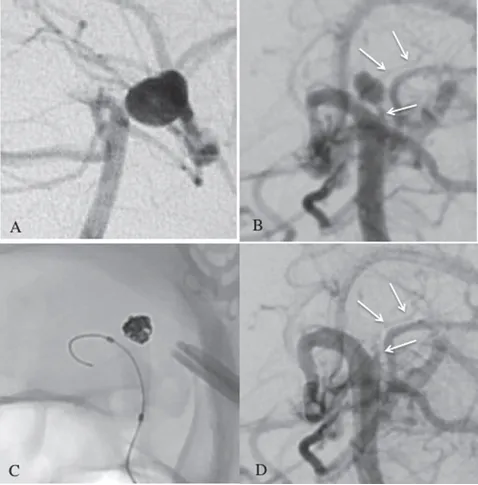

(A)既往DSA显示左侧PCA未通,无BA尖端动脉瘤。

(B)右侧椎体血管造影显示丘脑后穿通动脉(pTPA)动脉瘤。pTPA(白色箭头)起源于闭塞的左侧P1孔。

(C&D)采用六个弹簧圈实现了完全闭塞。弹簧圈栓塞后检测到丘脑后方穿通动脉(白色箭头)。